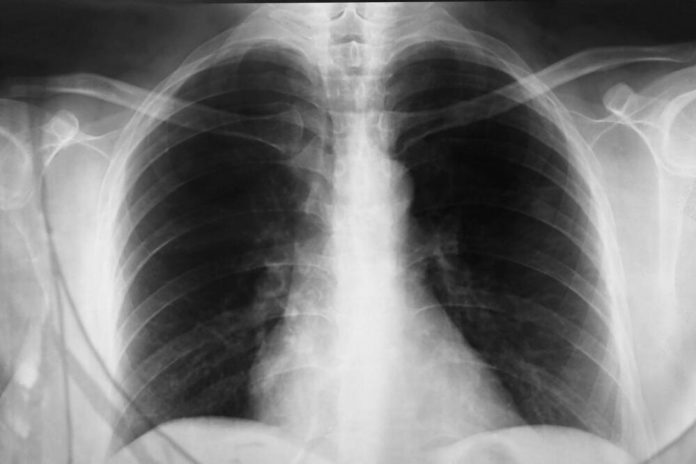

Kašalj i bol u plućima

Kašalj i bol u plućimafoto: Profimedia / observer / Alamy / Alamy /